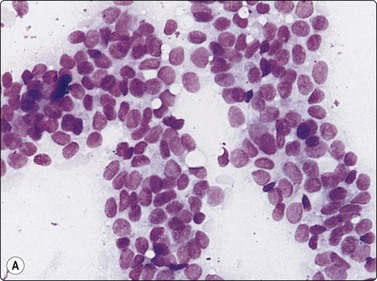

Hepatoblastoma177-181

Hepatoblastoma is a rare, highly malignant tumor of infants and young children, which metastasizes early. It is not associated with chronic liver disease. The alpha fetoprotein level is significantly raised in approximately 90% of cases. Patients can have a good response to surgery and chemotherapy. There is a spectrum of subtypes from anaplastic through embryonal and fetal to macrotrabecular, based on growth pattern and increasing resemblance of component cells from anaplastic towards hepatocyte morphology. A mixed epithelial and mesenchymal pattern includes primitive mesenchyme. The cytological appearance is that of a small round cell childhood tumor, (Fig. 10.28, and also Figs 17.1817.20), with clusters, ribbons and rosettes of embryonal cells, which are small cells with a high N : C ratio, oval to spindled nuclei, coarse chromatin, prominent, often multiple, nucleoli, and scant to moderate cytoplasm. Fetal epithelial cells, are slightly smaller than hepatocytes with round regular nuclei, fine chromatin, prominent central nucleoli and abundant granular or clear cytoplasm which may contain fat, bile or glycogen. Fragments of mesenchyme may be observed. Foci of extramedullary hemopoiesis are often present. The differential diagnosis is that of other small round cell childhood tumors metastatic to the liver or of HCC, which may occur in older children. HepPar-1 staining of hepatoblastoma can be useful in this regard.182

image

Fig. 10.28 Hepatoblastoma

Tumor tissue fragment, showing nuclear crowding and overlapping, increased nucleocytoplasmic ratios, irregular chromatin, minimal cytoplasm (MGG, HP).